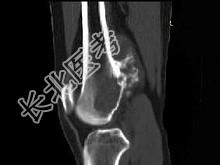

- 单项选择题男,34岁, 大腿下段疼痛2年,可摸到肿块, 结合图像,最可能的诊断是 ( )

A、骨肉瘤

B、软骨肉瘤

C、软骨瘤

D、纤维肉瘤

E、巨细胞瘤